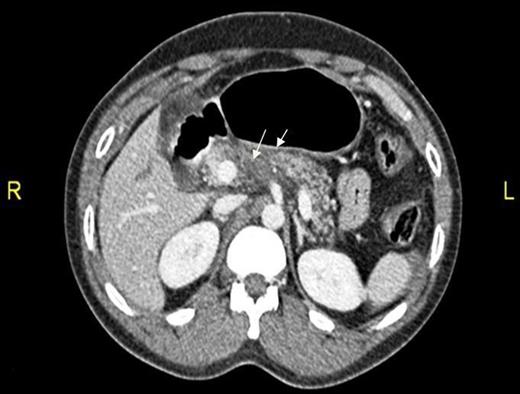

CT abdomen showing two hepatic lacerations in addition to minimal subhepatic and left subdiaphragmatic free fluid.

Definite management of pancreatic injuries is not well defined yet. Moreover, the clinical and laboratory findings of blunt pancreatic injury are nonspecific, and therefore accurate diagnosis in its acute phase is usually delayed [1, 3]. Computed tomography scanning may fail to delineate the pathology, especially in the initial stage. Also, the ability for CT to demonstrate the integrity of pancreatic duct is limited (43%); however, multiple detector computed tomography may have better result [1, 4, 5].